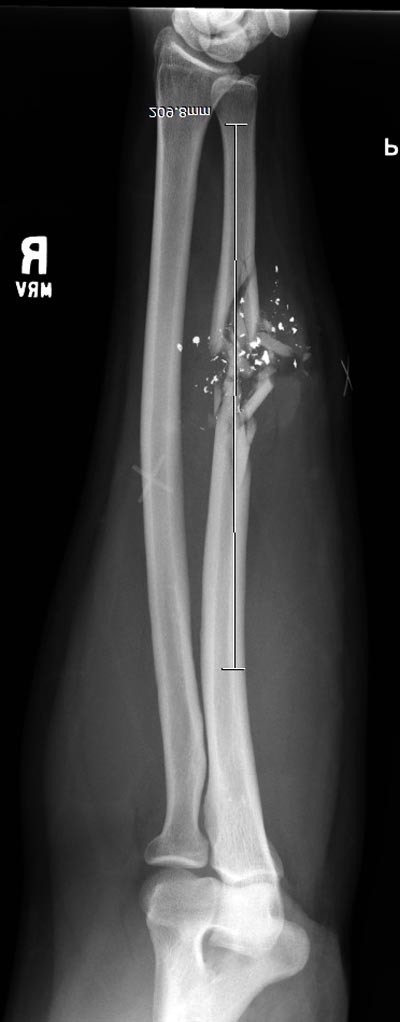

Здесь примеры: двоюродные братья с ранением предплечья, у одного локтевая, а у второго лучевая. В следующее утро локтевая фиксирована без обнажения фокуса травмы из небольших доступов, а второй из обычного волярного доступа. А клинический снимок из прошлых операций...